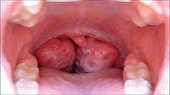

رایج‌ترین خوردنی‌ های آلرژی‌زا

۲۰ ارديبهشت ۱۴۰۲ - ۲۱:۰۲ | نظر

طیف وسیعی از غذاها می‌توانند منجر به آلرژی‌های غذایی شوند اما طبق گفته سازمان غذا و داروی ایالات متحده، هشت خوردنی باعث بیشترین واکنش‌های آلرژیک در افراد می‌شوند.